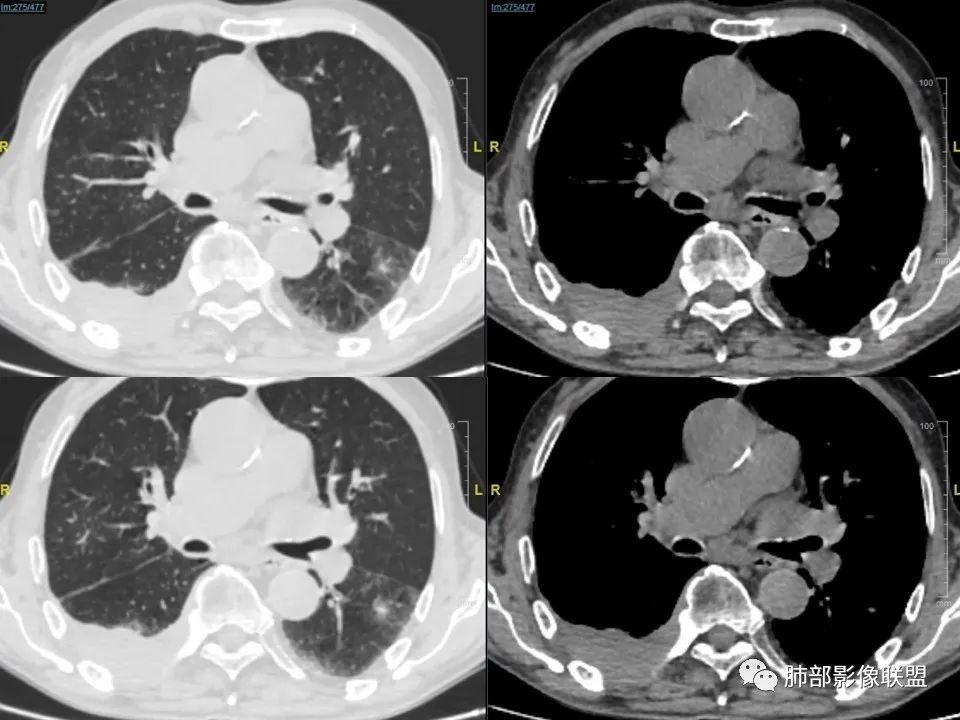

三明治征”之谜—胸膜淋巴瘤1例CT影像

老年男性,右侧胸膜软组织肿块延伸至后纵隔主动脉旁,平扫密度均匀稍高,增强扫描均匀强化,高于肌肉,其内血管走形包绕,部分包绕肋骨,考虑淋巴瘤。病人石棉接触史,不能除外间皮瘤(胸水应该更多)。

右肺下叶肿块,宽基底与胸膜相连,局部胸膜下间隙消失,肋骨未见明显骨质破坏,平扫密度均匀,增强后可见内部点片状强化,坏死囊变不明显,右肺叶裂旁多个小气囊,双肺多发模糊的小结节,老年男性,有石棉肺,综合考虑1:胸膜间皮瘤2:淋巴瘤3:结核瘤4:SFT

老年男性,咳嗽气喘纳差3个月,慢性病史,有石棉接触史。右下肺胸膜下巨大肿块,宽基底与胸膜相连,考虑来源胸膜,密度均匀,内有钙化,左侧胸膜增厚,有点状钙化,双肺野外带可见斑片影,多发囊泡,考虑恶性胸膜间皮瘤,慢阻肺。 医学百科网 | YxBaike.Com

患者老年男性,咳嗽、气喘、纳差3月(近3月体重下降10斤),既往史:中年时期有石棉接触史2年。慢性支气管炎病史6年,胆囊炎手术病史9年。心律不齐病史9年,脑梗塞病史2年余,血沉91mm/h。胸CT:右侧胸膜明显增厚,4R 7组淋巴结肿大。考虑恶性胸膜间皮瘤。

右后胸膜下团块,局部膨隆突起,增强扫描有强化,右侧肋间动脉供血,腹膜后主动脉旁亦见团块状软组织密度影,和主动脉分界不清,增强扫描有强化,有石棉工作史,体重明显下降,纵膈淋巴结明显增大,考虑恶性,胸膜间皮瘤?有点疑惑就是胸水不明显,鉴别淋巴瘤。两肺斑片状状影,考虑感染,其中右肺下叶局部结节状影,边缘稍毛糙,周围少许点片状影,首先考虑感染,不除外结核结节和腺癌可能。

石棉接触史,胸膜三明治征,考虑淋巴瘤,鉴别间皮瘤 医学百科网 | YxBaike.Com

1、老年男性,右侧后胸壁软组织肿块延伸范围较广(至后纵隔主动脉旁),平扫密度均匀稍高,增强扫描均匀强化,其间走行肋间动脉包埋、漂浮(夹心三明治),部分包绕肋骨,肋骨骨质未见明显吸收破坏! 医学百科网 | YxBaike.Com

2、胸膜掀起或尾征,胸壁肋间肌及脂肪间隙浸润,肋间动脉供血。 医学百科网 | YxBaike.Com

3、纵隔淋巴结多发肿大,部分有融合。

4、双侧未见典型胸膜斑,提示石棉非长期接触。胸膜病变不广泛。淋巴结改变与胸膜病灶不相称。 医学百科网 | YxBaike.Com

5、良性胸膜间皮瘤局限、规则高密度。恶性间皮瘤胸膜呈波浪状,常伴胸水。 医学百科网 | YxBaike.Com

6、老年患者转移瘤多见。双侧多发,易伴胸水。胸壁侵犯肋骨破坏为主。常有原发肿瘤。